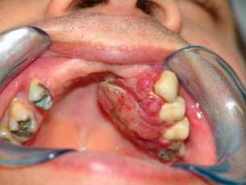

Un nuevo estudio del Instituto de Investigación y Datos (RDI) de Delta Dental of Michigan halló que, en Estados Unidos, el costo de los tratamientos para el cáncer en la cavidad bucal, faringe y glándulas salivales sería el más alto entre todos los tipos de cáncer en el país. Los detalles del estudio se darán a conocer hoy en la publicación de libre acceso Head and Neck Oncology de BioMed Central.